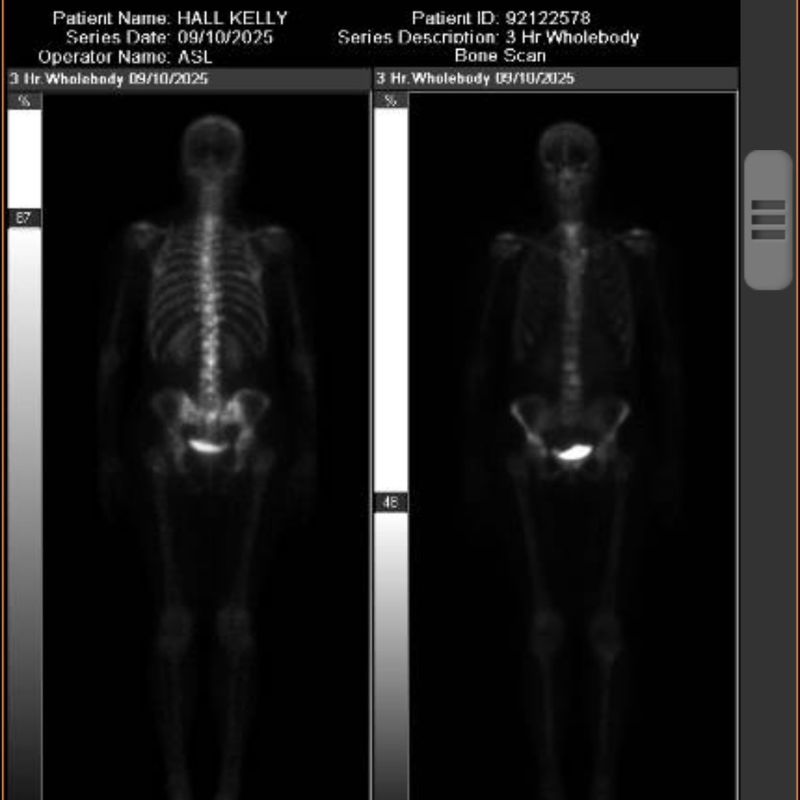

But four years ago, cancer roared back: tumors in my neck, armpits, lung, and skull, with lesions across my bones. The Stage IV diagnosis and “palliative” label were terrifying. Surgery, chemo, and radiation weren’t even part of the plan.

Instead, my big bet was on a new Novartis drug called Kisqali. I’ve taken it for four years now, on a schedule of three weeks on and one week off. The tumors are gone, and I feel great.